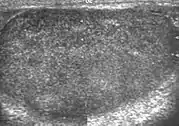

![]() Sonography of a normal testis. The normal testis presents as a structure having homogeneous, medium level, granular echotexture. The mediastinum testis appears as the

hyperechoic region located at the periphery of the testis as seen in this figure. | |

The normal adult testis is an ovoid structure measuring 3 cm in anterior-posterior dimension, 2–4 cm in width, and 3–5 cm in length. The weight of each testis normally ranges from 12.5 to 19 g. Both the sizes and weights of the testes normally decrease with age. At ultrasound, the normal testis has a homogeneous, medium-level, granular echotexture. The testicle is surrounded by a dense white fibrous capsule, the tunica albuginea, which is often not visualized in the absence of intrascrotal fluid. However, the tunica is often seen as an echogenic structure where it invaginates into the testis to form the mediastinum testis. In the testis, the seminiferous tubules converge to form the rete testes, which is located in the mediastinum testis. The rete testis connects to the epididymal head via the efferent ductules. The epididymis is located posterolateral to the testis and measures 6–7 cm in length. At sonography, the epididymis is normally iso- or slightly hyperechoic to the normal testis and its echo texture may be coarser. The head is the largest and most easily identified portion of the epididymis. It is located superolateral to the upper pole of the testicle and is often seen on paramedian views of the testis. The normal epididymal body and tail are smaller and more variable in position.